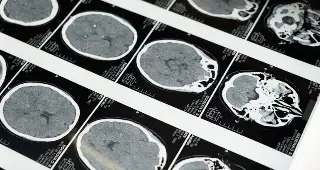

El consumir bebidas alcoholicas adulteradas te pueden generar alteraciones neurológicas muy severas, ceguera, incluso hasta la muerte, por lo que es importante evitar tomarlas.

Detalló que el metanol es la sustancia que más se utiliza para adulterar las bebidas, es un líquido que se usa de manera industrial para hacer los anticongelantes,  pinturas, entre otros.